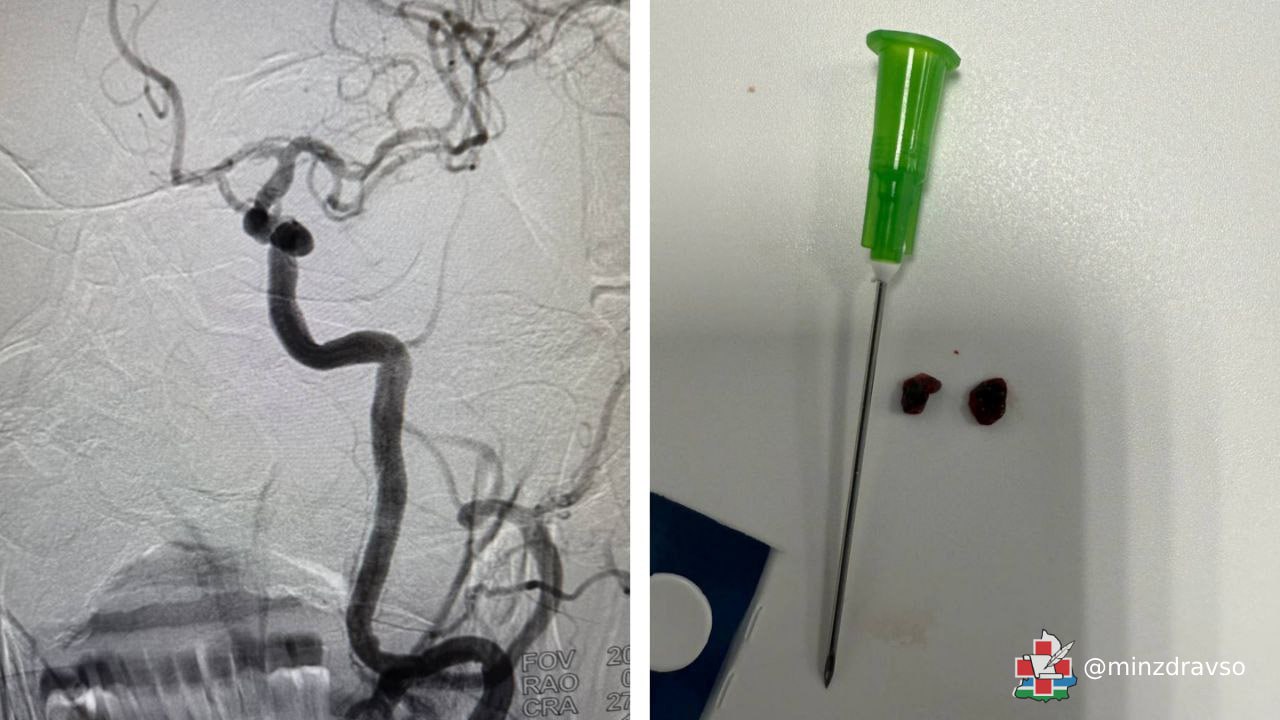

Выполнение тромбоэкстракции в одном из крупнейших межмуниципальных центров Свердловской области стало возможным после установки современного компьютерного томографа с функцией перфузии. Эта опция позволяет определить степень работоспособности мозга, если с начала инсульта прошло более пяти часов. Оборудование в Городской больнице Каменска-Уральского введено в эксплуатацию благодаря программе по борьбе с сердечно-сосудистыми заболеваниями национального проекта «Продолжительная и активная жизнь».

«Пациент 74 лет поступил к нам с полным параличом правой стороны тела, нарушением движения глазных яблок, отсутствием речи. Мужчину осмотрел невролог, с помощью компьютерной томографии были выявлены в одном сосуде две закупорки по 3 миллиметра. Мы провели тромболизис и сразу же начали тромбоэкстракцию через ангиограф. Оба тромба были удалены, физические функции мужчины начали восстанавливаться в этот же день», — рассказал заведующий отделением рентгенохирургических методов диагностики и лечения Городской больницы Каменска-Уральского Кобилжон Джураев.

Хирург объясняет, что сейчас у пациентов, перенёсших инсульт, гораздо больше шансов на выздоровление, так как тромболизис может растворять только небольшие закупорки и только в первые 4,5 часа с начала характерных симптомов. Тромбоэкстракция позволяет справляться с более крупными сгустками, в том числе, когда невозможно установить время начала сосудистой катастрофы.